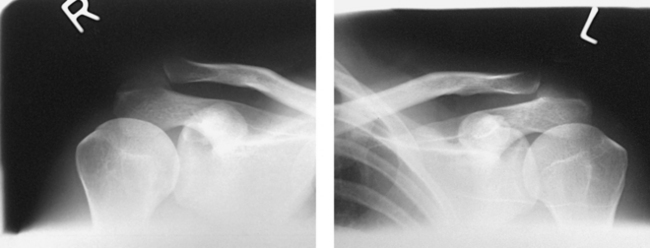

Structures shown: Bilateral images of the AC joints are shown (Figs. 5-56 and 5-57). This projection is used to show dislocation, separation, and function of the joints.